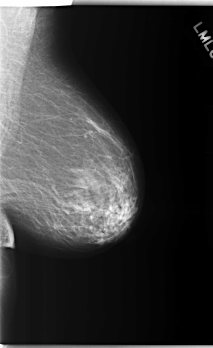

C_0275_1.RIGHT_MLO

RIGHT_CC LINES 5928 PIXELS_PER_LINE 3664 BITS_PER_PIXEL 12 RESOLUTION 50 NON_OVERLAY